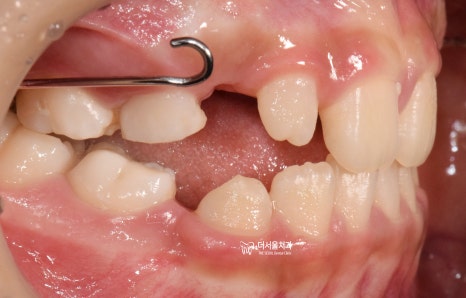

정면 사진 및 측면 안모 사진에서,

느껴지는 것들이 있습니다.

첫번째, 주걱턱의 경향

두번째, 얼굴이 길게 느껴짐

얼굴이 길게 느껴지는 거는,

사진으로만 봤을 때는 치아의 문제입니다.

즉, 교합 관계만 올바르게 맞춰주면

아래턱이 위로 올라갈 거 같네요.

다만, 주걱턱의 경향은 골격성의 문제기 때문에

성장교정 을 통해서 위턱과 아래턱의

균형이 맞아야 개선이 되는 상황이였습니다.